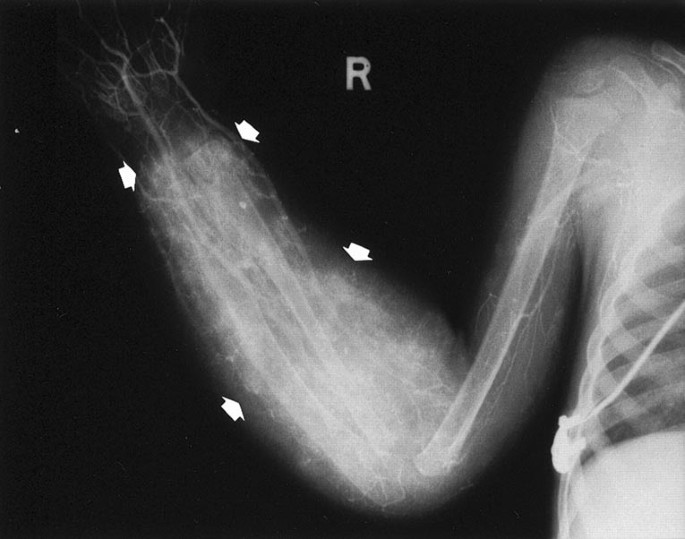

This case was previously reported, and only the cutaneous lesions and the follow-up are described here (11). This 5-month-old boy presented with a small skin nodule on the right antecubital fossa, and the diagnosis of hemangioma and hemangiopericytoma was made on the excision. He returned a year later with a swollen right forearm, and extensive soft tissue tumor infiltration including the distal radius and ulna (Fig. 1). Only two small cutaneous purplish nodules, each of less than 1 cm, were apparent at the old biopsy site and other on the distal lateral aspect. An above-elbow amputation was performed for the uncertainty regarding the nature of the tumor, and for a severe Kasabach-Merritt syndrome. The boy was rehabilitated with an artificial limb. He has been disease-free for 16 years of follow-up.

Patient 1. The markedly swollen forearm was due to diffuse ill-defined small vascular nodules in the soft tissues shown in angiogram (arrows). × 0.8 of actual size.